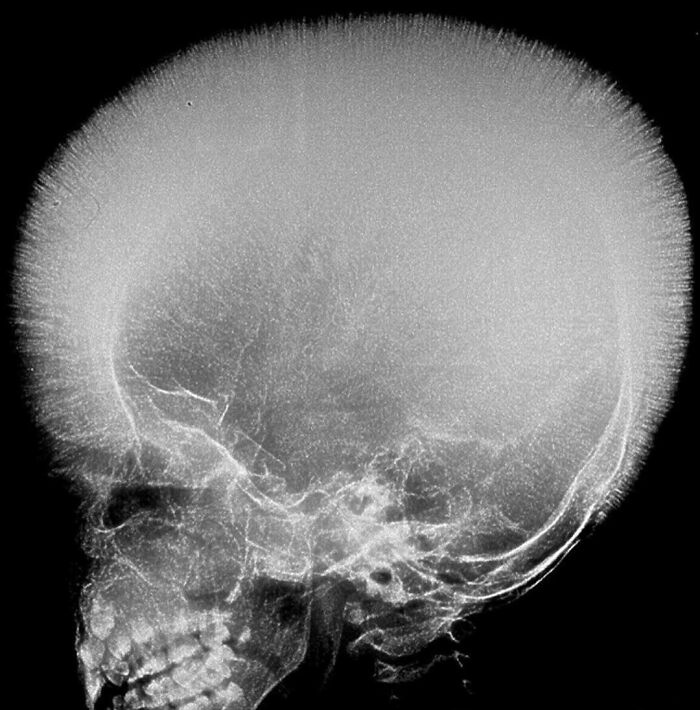

Lateral view skull radiograph of a patient with multiple myeloma

The classic radiographic appearance of multiple myeloma is that of multiple, small, well-circumscribed, lytic, punched-out, round lesions within the skull, spine, and pelvis. The pattern of lytic or punched-out radiolucent lesions on the skull have been described as resembling raindrops hitting a surface and splashing. How would you manage a patient with multiple myeloma?